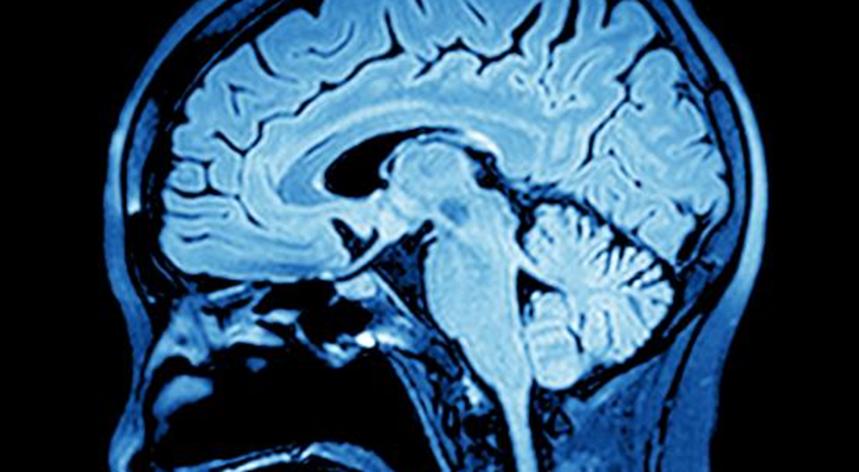

根據醫療保健行業(yè)的一份報告,隨著(zhù)醫療保健行業(yè)向提供更多個(gè)性化護理的轉變,由于新技術(shù),如AI和深度學(xué)習,臨床決策支持軟件,傳感器,3D打印和精度分析,精密醫學(xué)成像市場(chǎng)可能會(huì )出現巨大增長(cháng)。弗羅斯特&沙利文。

報告稱(chēng),隨著(zhù)新興技術(shù)的發(fā)展,到2027年,醫學(xué)成像市場(chǎng)預計將超過(guò)80億美元。2017年市場(chǎng)達到1.2億美元。

該報告分析了醫學(xué)影像市場(chǎng)的增長(cháng)機會(huì ),以及如何將這些機會(huì )應用于成像的各個(gè)階段,例如研究訂購,圖像采集和圖像解釋。